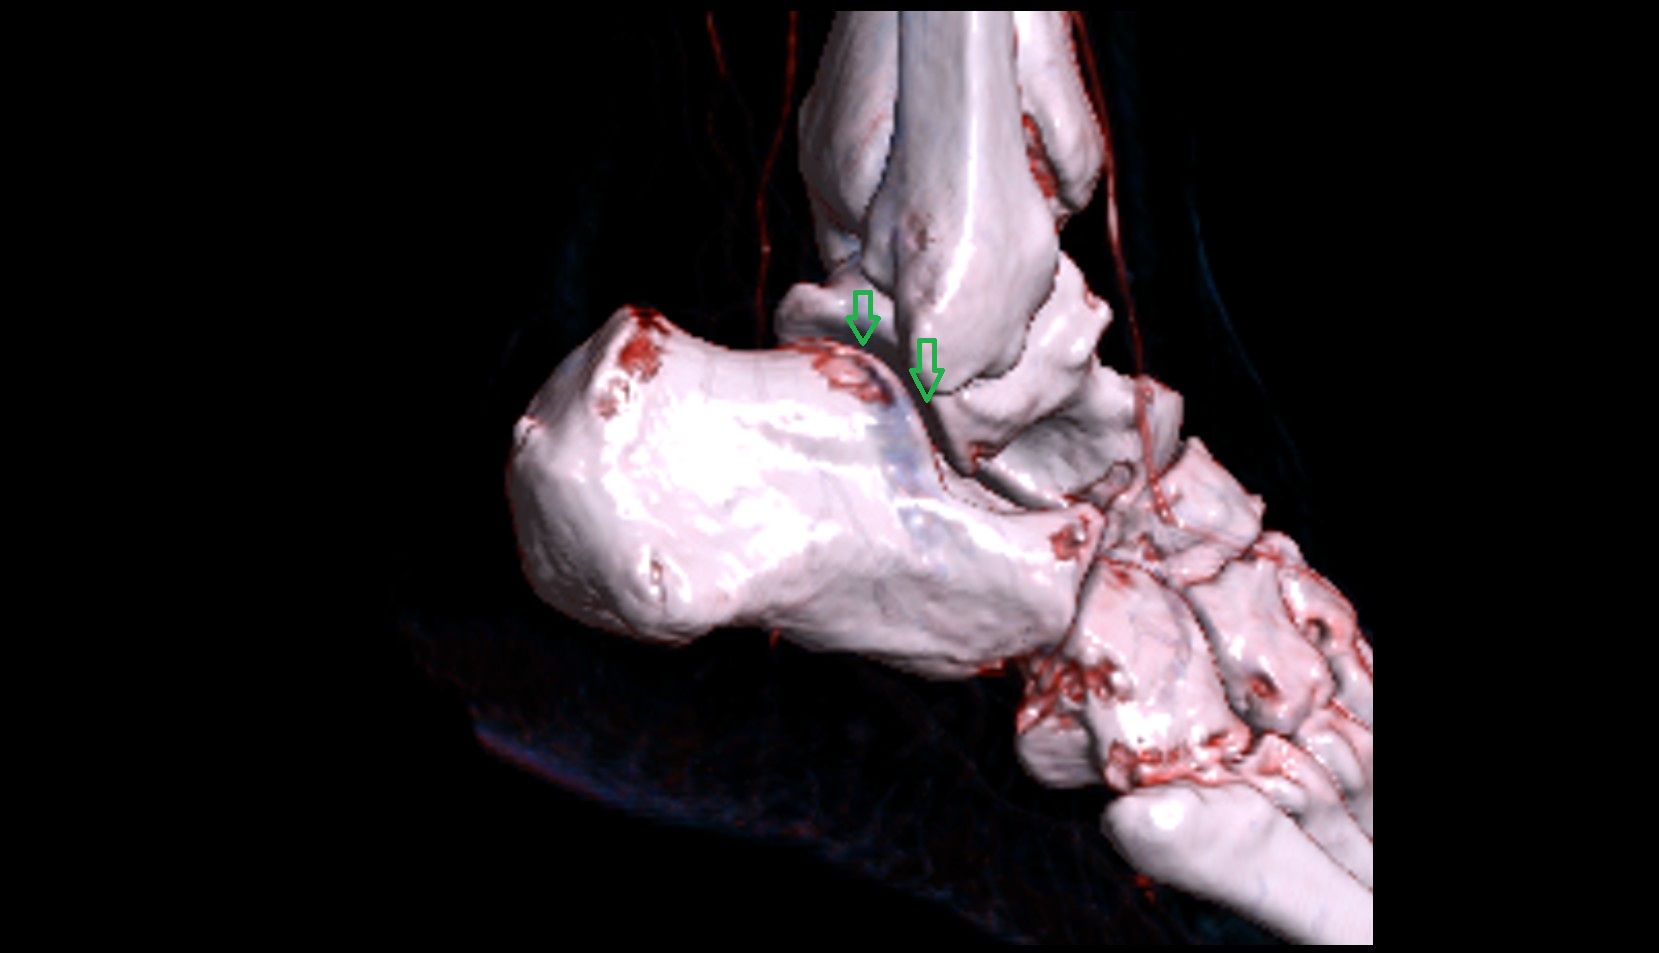

- Talus

- Head of talus

- Body of talus

- Neck of talus

- Calcaneus

- Medial malleolus

- Lateral malleolus

- Ankle joint